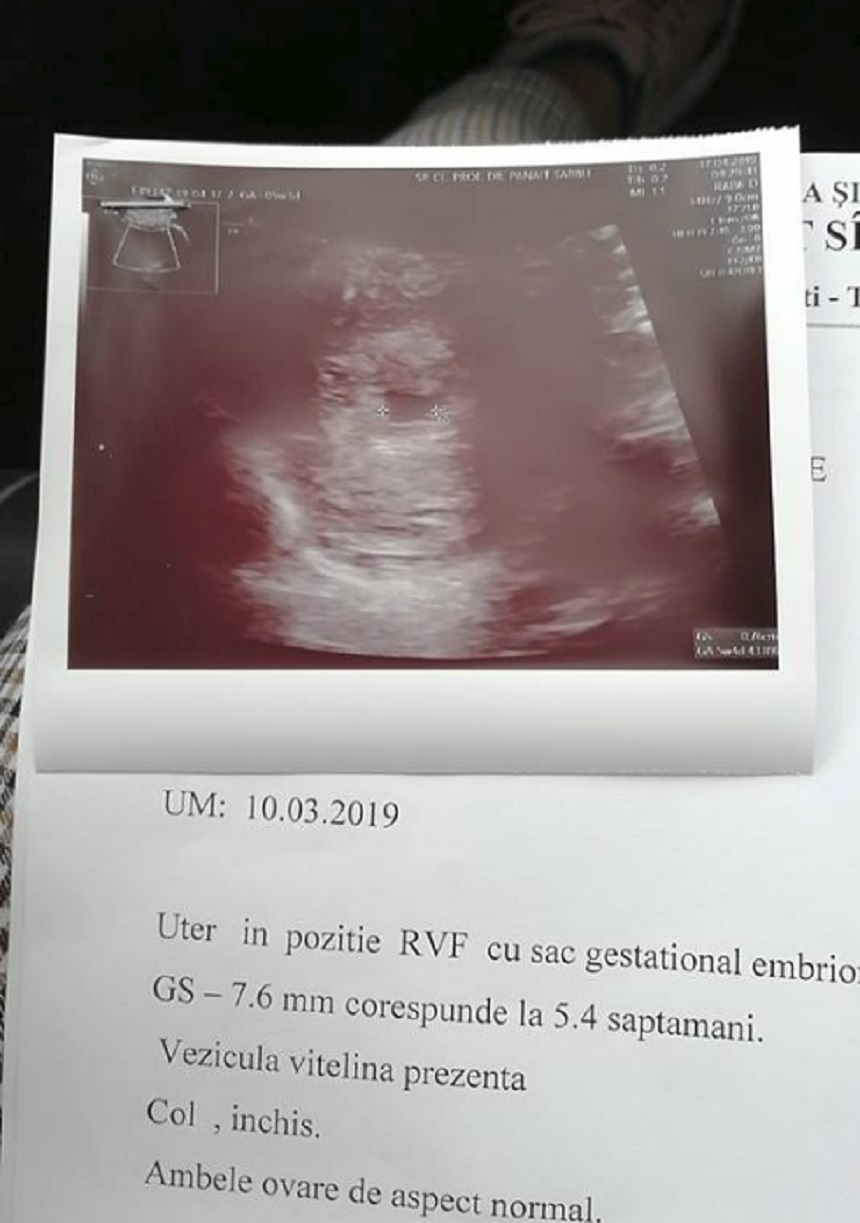

Florin Măxineanu a dat vestea cea mare chiar în ziua în care își aniversa ziua de nume, în duminica Floriilor. Îndrăgitul artist a publicat două fotografii, una cu el și soția și una cu ecografia.

Extrem de fericit, Florin Măxineanu a dat tuturor vestea cea mare "❤️✌️💪 Noi si Lușu-Băbălușu❤️".